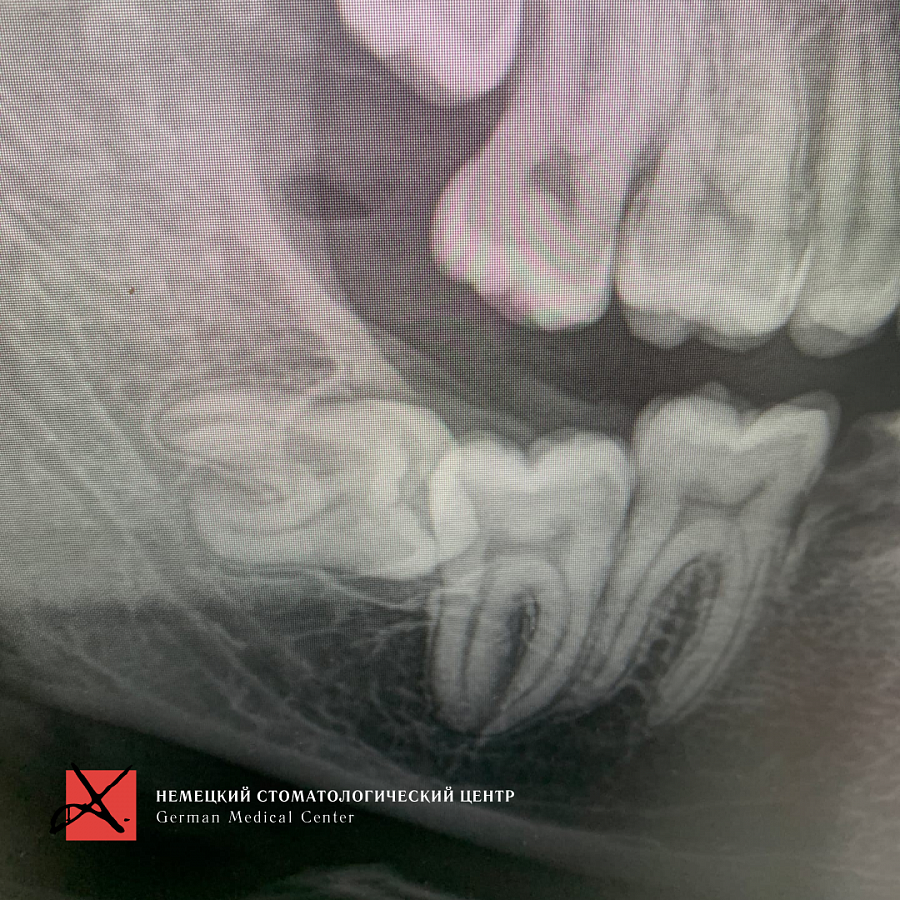

Пациент направлен врачом-ортодонтом для удаления зуба мудрости, который лежит горизонтально. Зуб мудрости мешал прорезаться седьмому зубу.

Доступ к восьмому зубу был сильно ограничен, что усложняло удаление. Но наш хирург успешно справился с задачей.